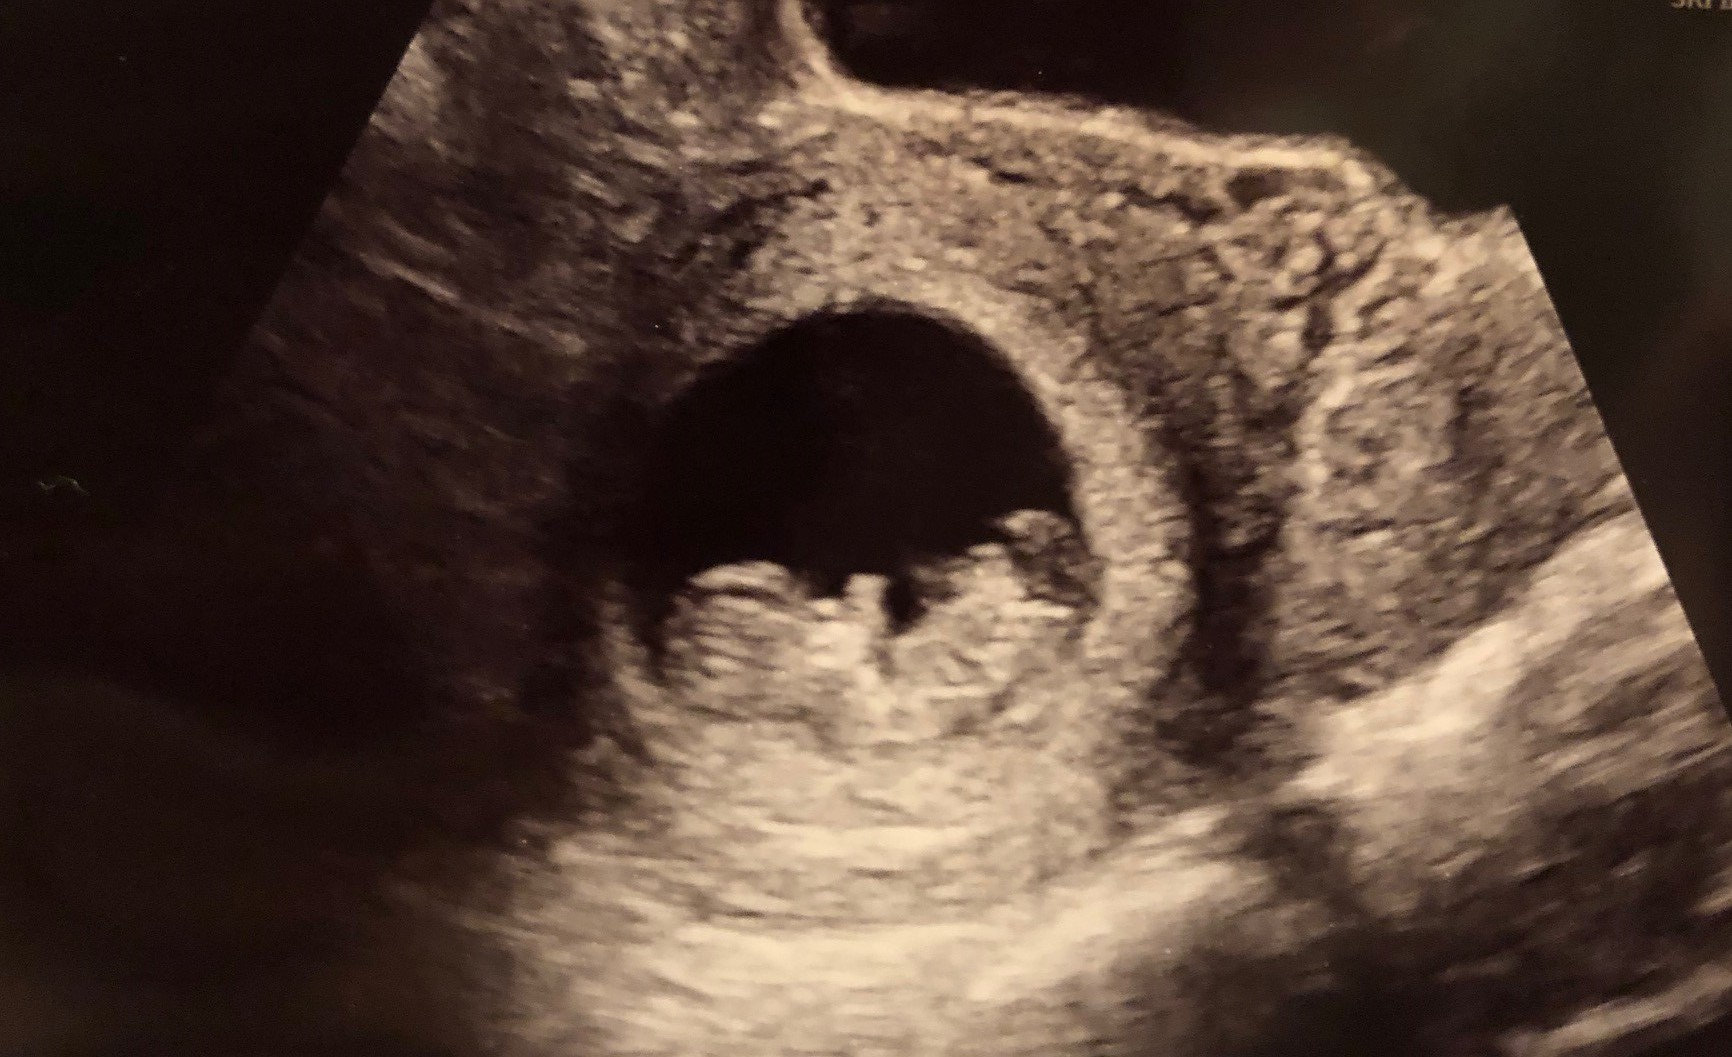

Had another ultrasound Sunday at the ER I was 9w2d and I had pain and bleeding. They found a hemorrhage but baby was doing good HR was 170 and the baby even looks like they’re smiling!